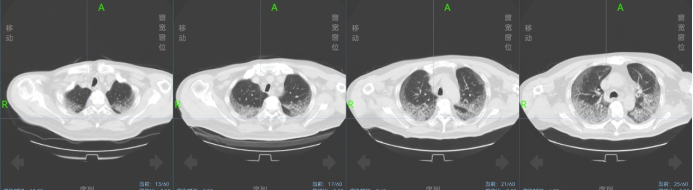

12月2日患者病情突然变化,出现间断气短、血氧有所下降,指脉氧饱和度下降至80%~85%,高流量吸氧FiO2调整到100%,氧流量50 L/min,指脉氧饱和度可升高到94%。血气分析:pH 7.50,PaO2 61.00 mmHg,PaCO237.0 mmHg,剩余碱5.5 mmol/L,实际碳酸氢根28.90 mmol/L,氧饱和度93%。复查胸CT提示左侧气胸(图4,追问患者情况,患者诉有饮水后剧烈呛咳史;立即行胸腔闭式引流术。

图4  2022年12月3日胸部CT